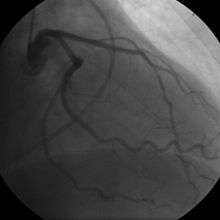

- Coronary angiography

In "stable" angina, chest pain with typical features occurring at predictable levels of exertion, various forms of cardiac stress tests may be used to induce both symptoms and detect changes by way of electrocardiography (using an ECG), echocardiography (using ultrasound of the heart) or scintigraphy (using uptake of radionuclide by the heart muscle). If part of the heart seems to receive an insufficient blood supply, coronary angiography may be used to identify stenosis of the coronary arteries and suitability for angioplasty or bypass surgery.

Diagnosis of acute coronary syndrome generally takes place in the emergency department, where ECGs may be performed sequentially to identify "evolving changes" (indicating ongoing damage to the heart muscle). Diagnosis is clear-cut if ECGs show elevation of the "ST segment", which in the context of severe typical chest pain is strongly indicative of an acute myocardial infarction (MI); this is termed a STEMI (ST-elevation MI), and is treated as an emergency with either urgent coronary angiography and percutaneous coronary intervention (angioplasty with or without stent insertion) or with thrombolysis ("clot buster" medication), whichever is available. In the absence of ST-segment elevation, heart damage is detected by cardiac markers (blood tests that identify heart muscle damage). If there is evidence of damage (infarction), the chest pain is attributed to a "non-ST elevation MI" (NSTEMI). If there is no evidence of damage, the term "unstable angina" is used. This process usually necessitates admission to hospital, and close observation on a coronary care unit for possible complications (such as cardiac arrhythmias – irregularities in the heart rate). Depending on the risk assessment, stress testing or angiography may be used to identify and treat coronary artery disease in patients who have had an NSTEMI or unstable angina.